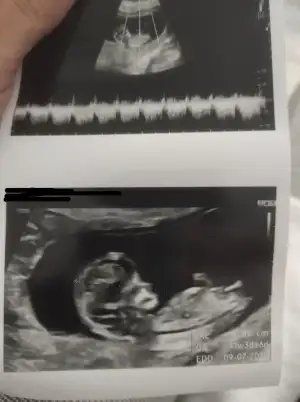

dr soylemeden siz gorun genital nub teorisi ( bebegin cinsiyeti)

• IMG_20211213_173510.webp

IMG_20211213_173510.webp

12,2 KB · Görüntüleme: 53

• C37EED34-1F99-4CD5-BC35-CA7C1502474E.webp

C37EED34-1F99-4CD5-BC35-CA7C1502474E.webp

171,3 KB · Görüntüleme: 58

• 886473DA-D753-4C11-9151-C34003504FF9.webp

886473DA-D753-4C11-9151-C34003504FF9.webp

22,5 KB · Görüntüleme: 62